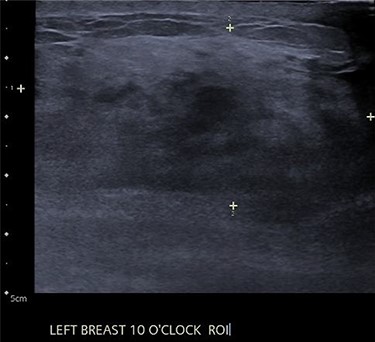

A 39-year-old south Asian female (AB) presented with a 5-cm left breast mass at the 10 O’clock position, increasing in size and tenderness but systemically well with no axillary lymphadenopathy. Examination of the right breast was unremarkable. Previous history included two children and a left breast abscess 1 year prior, which was aspirated under ultrasound. There was no family history of malignancy or other risk factors.

An ultrasound of the left breast demonstrated a 60-mm irregularity with no underlying collection at the 10 O’clock position, 2 cm from the nipple (Fig. 1). AB was treated with 5 days of oral flucloxacillin for presumed mastitis, and underwent a bilateral mammogram and ultrasound due to the suspicious irregularity of the left breast lesion. This showed an area of asymmetric density in the medial left breast with hyperemia (Fig. 2). The right breast showed two clusters of pleomorphic microcalcifications in the upper outer quadrant, further characterized as irregular lesions measuring 16 × 11 × 11 mm and 9 × 10 × 7 mm (Fig. 3).